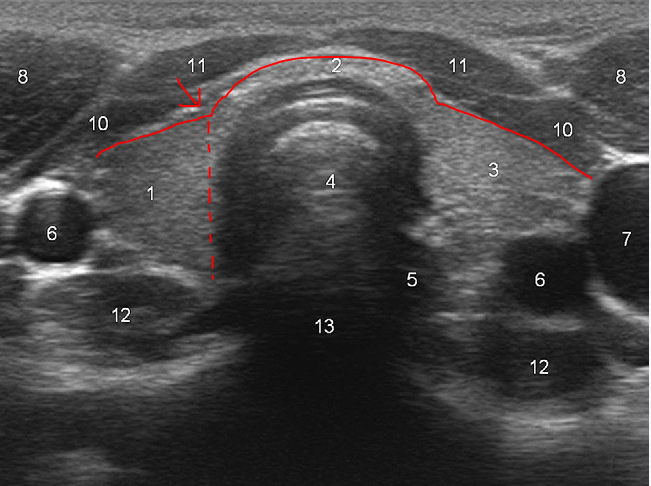

[ 표준영상 ]

1. Isthmus를 가운데 포함한 전체 갑상선 axial view